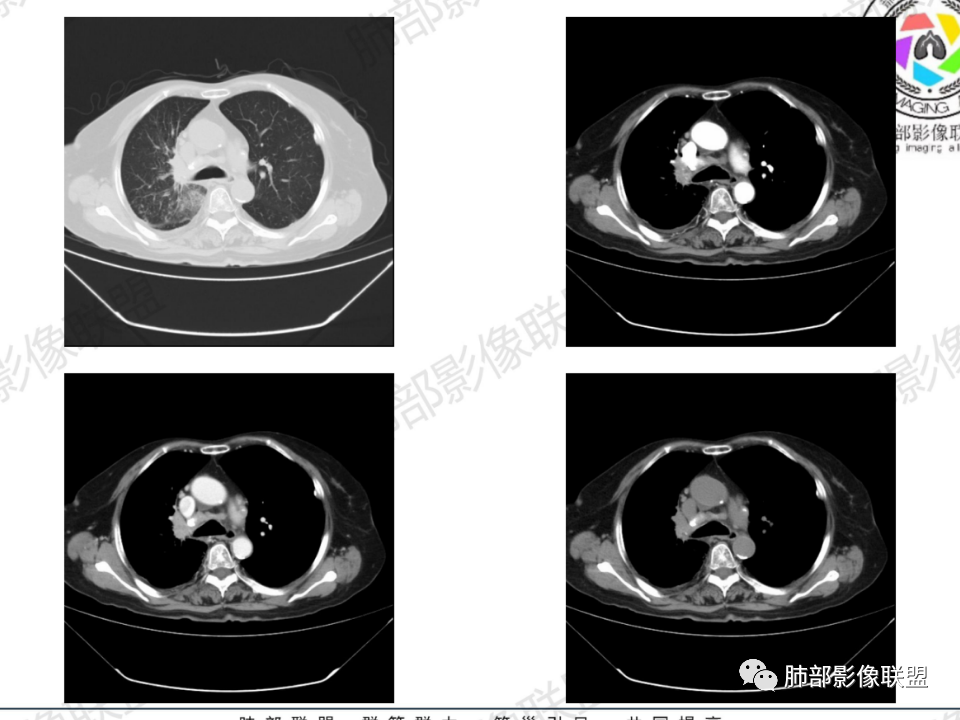

那个人:老年女性,亚急性病程,咳嗽发热。有垂体前叶功能减退,目前激素替代治疗,长期激素,量小,不知道累积量,没有目前激素水平指标。既往有淋巴结结核病史。肿瘤标记物Ca125升高。血沉升高,C反应蛋白轻度异常。影像,右肺上叶靠近肺门团块影,右肺门淋巴结钙化肿大,支气管狭窄,局部增厚,团块影外朝内改变,强化明显,血管破坏不明显,有粘液。和纵隔胸膜分界清楚,周围肺组织有斑片渗出影,右侧胸腔积液,考虑炎性?结核?支气管镜检查除外恶性飞鹰行动:老年患者,影像表现 右肺上叶占位性病变,边界清楚,有分叶征,内见细小钙化,右肺上叶支气管截断,增强病灶不均匀强化,病灶内有条状坏死区(扩张的支气管?),纵膈内未见增大淋巴结,考虑炎性病变,结核可能。一切∮随缘:右肺上叶实性肿块形态不规则,呈三角形,边缘分叶,边界伴有磨玻璃影,近段支气管未见明显显示,可能堵塞,病变平扫密度均匀,增强后可见低密度坏死无强化,周围略强化,右肺下叶散在结节。心包积液,及右侧胸腔积液,临床:有低热,低蛋白血症,肿瘤标记物高,考虑恶性:腺癌,神经内分泌癌(强化偏弱了),淋巴瘤,鉴别:结核红星:老年女性患者右肺上叶,肺门上区 分叶状肿块 ,右肺上叶支气管显示不清,增强扫描肿块,中等程度强化可见小斑片状坏死区,病灶内部可见斑点状钙化灶,病灶周围可见斑片状及小斑点状影,纵膈淋巴结增大,其他区域,胸膜下可见斑点状钙化。考虑肉芽肿性病变,结核的可能性大。老年患者最排除肿瘤性病变腺癌。土娃:右上肺不规则肿块影,边缘分叶,边界磨玻璃影欠清,病灶分叉状,内见点状钙化影及坏死灶,支气管堵塞,病灶增强强化不明显。考虑瘤样结核,鉴别淋巴瘤。张小兵:老年女性,亚急性病程,右肺上叶见不规则肿块,边缘平直凹陷为主,周围GGO边界不清,内见点状钙化及坏死灶,增强持续性渐进强化,右侧少量胸腔积液,双肺门及纵隔肿大淋巴结伴钙化,综合考虑慢性炎症。saf:老年患者,影像表现 右肺上叶占位性病变,边界清楚,有分叶征,增强病灶明显不均匀强化,纵膈内未见增大淋巴结,考虑炎性病变,结核可能。小兜:老年女性,咳嗽喘息一月,发热三天,肿瘤标志物升高,长期激素替代治疗。CT示右肺上叶近肺门不规则实变影,周围伴磨玻璃影,增强持续性渐进强化,内部血管破坏不厉害,内部可见多发条形低密度灶,右侧胸腔可见少量积液,双肺门及纵隔可见钙化淋巴结,考虑为炎性病变,结核可能玫:女,79咳嗽,喘息一月,发热三天入院,右肺上叶不规则形软组织密度肿块影,边界清晰,边缘见分叶及细短毛刺,病灶内见点状钙化影及稍低密度区,病灶边缘呈磨玻璃样改变,增强扫描,病灶呈不均匀性强化,考虑炎性病变,鉴别鳞癌。大雄:老年女性,既往诊断淋巴结结核,提示已治愈,近2年服用激素,诱导结核复燃→发热;纵隔肺门淋巴结肿大钙化,压迫支气管,右肺上中下叶支气管均狭窄→喘息咳嗽;尖段支气管受累闭塞→肺不张、支气管粘液栓;累及胸膜,结核性胸膜炎并胸水→右侧胸痛;实验室,血沉快,CA125高,低蛋白,符合;下一步,支气管镜尖段支气管刷检抗酸染色周太狼:老年女性,亚急性病程,肿瘤标志物升高。CT示右肺上叶尖段不规则肿块影,有分叶、收缩,周围伴磨玻璃影,增强渐进强化,内部可见多发条形低密度灶,右侧胸腔及心包少量积液,纵隔内淋巴结稍增大。倾向于恶性病变,肺癌伴阻塞性炎变可能。丽:老年女性,右肺上叶不规则软组织肿块,边缘清晰,内密度不均,可见点状钙化及粘液栓,周围可见片状高密度影,增强后均匀强化,内多发低密度,纵膈多发钙化淋巴结,考虑结核可能大,建议结合支气管镜检查除外肿瘤宇宙:右胸廓缩小,右肺上叶团块影及不张,平直边,周围磨玻璃影,纤细胸膜牵拉,上叶尖段支气管堵塞,明显延迟强化,可见支气管粘液栓,两肺门钙化淋巴结,右侧胸水,考性炎性肉芽肿,鉴别腺癌王秀仙:右肺上叶肺门区肿块,上叶支气管开口阻塞,形态不规则,密度不均,内可见支气管粘液栓及多发小灶性坏死,周围磨玻璃影边缘模糊,渐进强化,右侧胸腔积液、胸膜钙化,考虑炎性肉芽肿性病变,慢性炎症。鉴别鳞癌,结核。刘丹:老年女性,右肺上叶肿块伴钙化,右肺上叶支气管截断,增强后均匀强化,周边可见点片状模糊影,右侧胸腔积液,右肺门淋巴结增大,考虑占位并阻塞性炎症,肿瘤?结核?建议纤支镜检查。小飞:右肺上叶纵隔旁软组织肿块,边缘深分叶、长毛刺及毛刷样短毛刺,边缘磨玻璃影,磨玻璃边界模糊,支气管截断,平扫密度不均,可见点状钙化,增强不均匀明显强化,心影增大,心包积液,右侧胸腔积液,考虑恶性肿瘤,腺癌?秦化君:右肺上叶不规则分叶软组织密度肿块,边缘清晰,胸膜牵拉,周围花花草草,上叶尖段支气管阻塞,内可见点状钙化,增强后密度不均可见支气管粘液栓及坏死区,内见血管分枝。中间段及中叶,下叶支气管狭窄,壁见钙化。右肺门淋巴结肿大,右侧胸腔积液,心包粘连肥厚。考虑1右上肺恶性病变,鳞癌?2右肺多叶段支气管狭窄,考虑支气管内膜结核?3胸腔积液及肺门淋巴结肿大,转移?风儿:老年女性,右肺上叶肿块,形态不规则,外围大内带小,边缘分叶膨隆平直及毛糙,密度不均,内见支气管粘液栓及多发小灶性坏死,坏死边缘清晰 ,渐进强化,上叶尖段支气管阻塞,叶支气管壁有局限性增厚,邻近胸膜腔微积液;纵隔及双肺门淋巴结肿大,部分钙化,右侧胸腔积液、心包积液、胸膜钙化,考虑炎性,肉芽肿性结核可能性大。鉴别鳞癌,女性及血供均不支持;腺癌,坏死边界太清晰。流心明智:老年女性,79岁,咳嗽、气短1月,发热3天。胸CT:右肺上叶见不规则肿块,边缘有膨隆、有平直凹陷,周围GGO边界不清,病灶内见点状钙化、粘液栓,尖段支气管未见,增强持续性渐进强化,右侧少量胸腔积液,双肺门及纵隔肿大淋巴结伴钙化,肺动脉增粗。考虑:右上叶尖段堵塞并慢性炎症,支气管TB并结石?鉴别Ca

临床信息:老年女性,亚急性病程,咳嗽发热。有激素使用史。既往有淋巴结结核病史。肿瘤标记物Ca125升高。血沉升高,C反应蛋白轻度异常。 影像所见:右侧胸廓相对狭小,右肺上叶不规则团块影贴附纵隔旁,轻度分叶,整体密度较均匀,偶见钙点。

相应上叶尖端及前段支气管开口未能追踪(阻塞),开口处见钙化。病灶渐进性强化,并衬托出较完整尖段及前段含液支气管影。支气管开口区域未见异常高密度强化(如类癌等)及相对乏血供区(如鳞癌)。病灶区未见液化坏死。右上纵隔及胸廓入口区未见病灶胸膜外突破(栽赃)。

右肺上叶后段等区域散在片状影,边界不清(提示渗出性病灶)。

纵隔及双肺门见钙化淋巴结。心包积液,右侧胸腔积液(提示存在活动新病灶)。双侧胸膜下见多发斑点状钙化,胸廓变形(提示存在结核基础病变可能)。 诊断意见:综上,右肺上叶块状影更符合继发性肺结核。 最后小结:既往诊断淋巴结结核,提示已治愈。近2年服用激素,可疑诱导结核复燃,也可引起发热。纵隔肺门淋巴结肿大钙化,压迫支气管,右肺上中下叶支气管均狭窄,所以引起喘息咳嗽。尖段支气管受累闭塞,导致肺不张、支气管粘液栓,出现条状无强化区。病变累及胸膜,导致结核性胸膜炎并胸水,引起右侧胸痛。实验室检查血沉快,CA125高,低蛋白,均符合结核。下一步,建议支气管镜尖段支气管刷检并抗酸染色。(本段摘自於雄老师精彩发言)